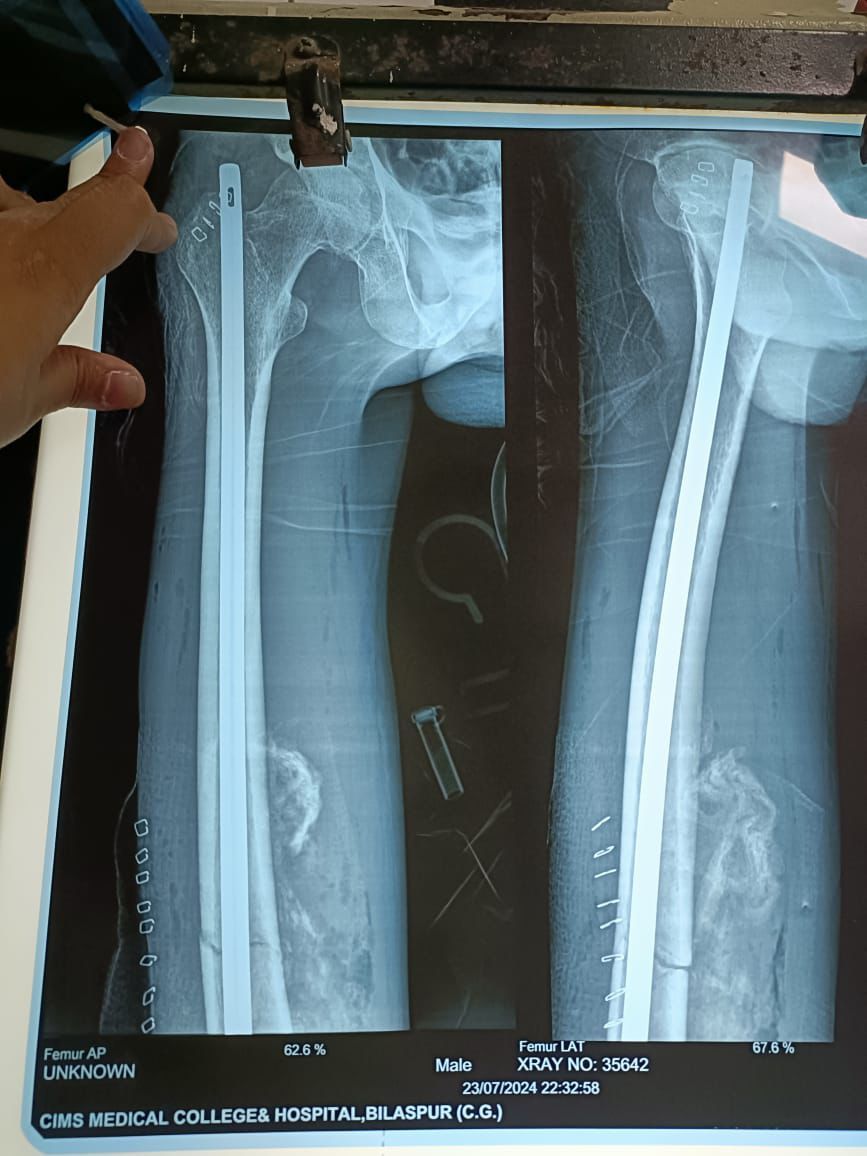

2 अज्ञात उम्र 40 साल जो 24 जून2024 को जिला अस्पताल कबीरधाम से रेफर होकर सिम्स भर्ती कराया गया । जो मरीज लावारिस था पैसों के अभाव में इलाज नहीं हो पा रहा था। सिम्स में इलाज डॉक्टर दीपक जांगड़े ने पूरा इलाज निशुल्क निस्वार्थ भावना से से किया और उनके पूरे टीम ने एनेस्थीसिया डॉक्टरों की टीम डॉ राकेश निगम के मार्गदर्शन में सफल ऑपरेशन हुआ इस पूरे ऑपरेशन पर डॉक्टर को बधाई सिम्स के अधिष्ठाता डॉक्टर के के सहारे ने दी।